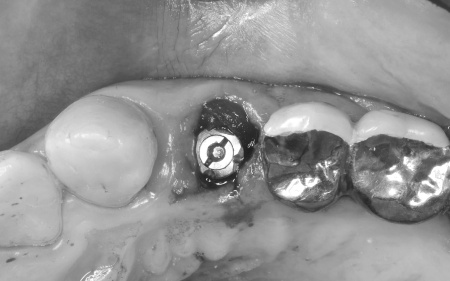

治療前

治療中